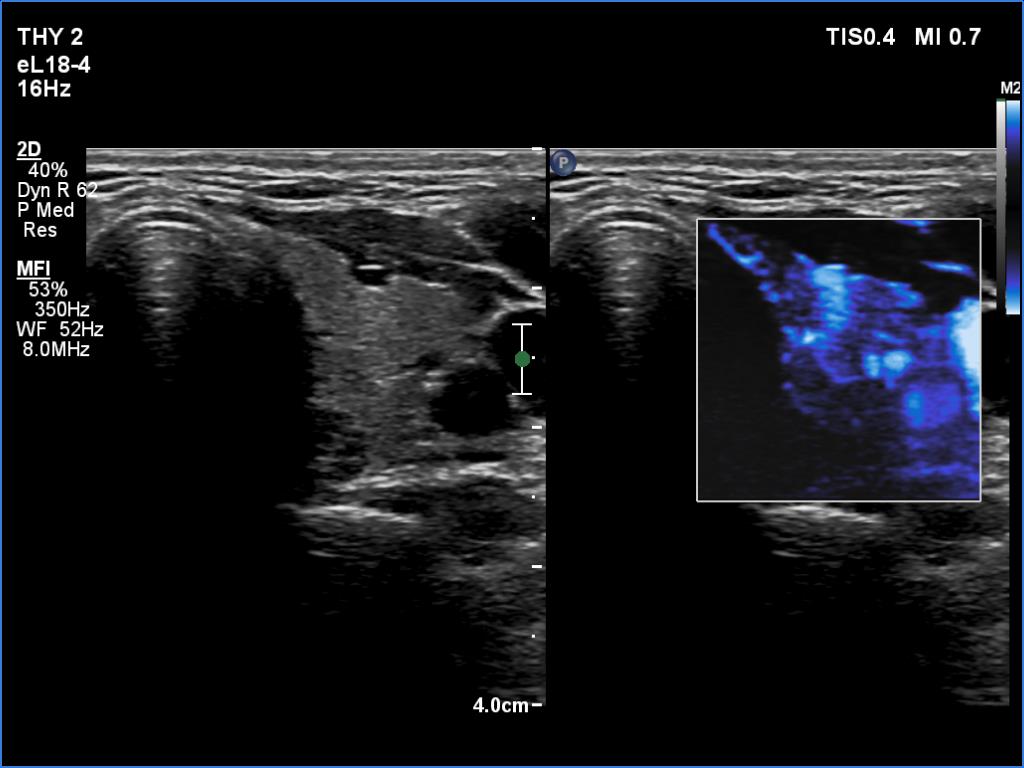

Right lobe, longitudinal scan

Left lobe, transverse scan, microflow imaging.